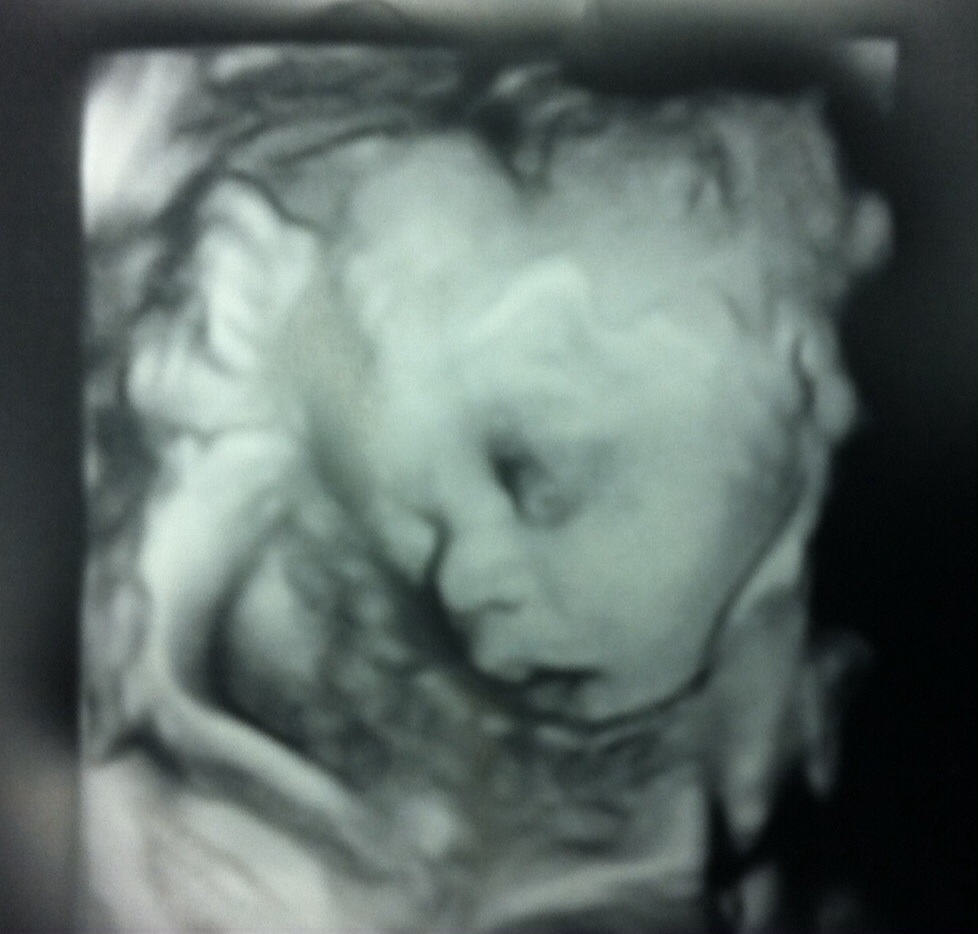

BFP 4/2013, Our Christmas Miracle Due 12/18/2013